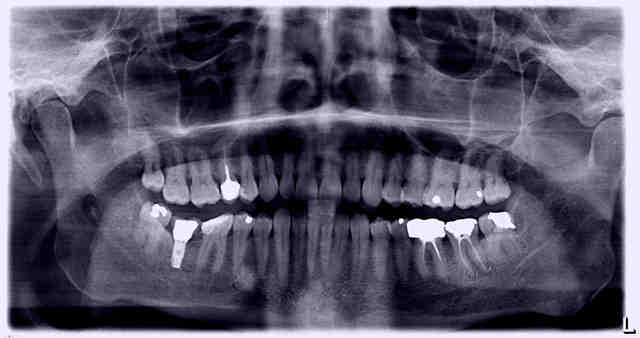

Bjr, je cherche à savoir quel est cet implant.

La CCM trans vissée est mobile, je vais dévisser et changer de vis.

A priori c'est du strauman WP ?, mais c'est un peu limite pour commander la nouvelle vis et trouver la clef qui va bien.

sur ce n'est pas du straumann. nobel hexagone externe rp ou wp. radio pas trop top